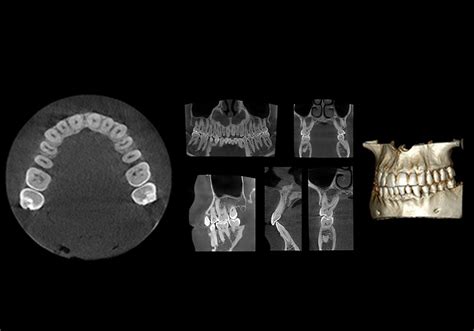

- TC dental: Es una prueba radiológica que consiste en obtener imágenes tridimensionales de los huesos maxilares de alta definición anatómica (dientes, huesos, trayecto del nervio dentario), mediante el empleo de un equipo de TC (Tomografía Computarizada). La tomografía computarizada dental permite visualizar imágenes de alta resolución de contraste y en los planos axiales, coronales y sagitales. Esto ayuda a tener un diagnóstico más detallado para el tratamiento bucal adecuado.

Tecnología CBCT en Radiología Dental

La tecnología CBCT (Cone Beam Computed Tomography) también ha revolucionado la radiología dental, proporcionando imágenes tridimensionales detalladas y precisas de la estructura dental y facial. Los equipos CBCT son una forma avanzada de tecnología de imagen que utiliza un cono de rayos X en forma de abanico para obtener imágenes tridimensionales de las estructuras orales. Esto es útil para seleccionar el tratamiento que mejor se ajuste a las necesidades y expectativas del paciente, pero no solo cuando si intención es la ortodoncia.